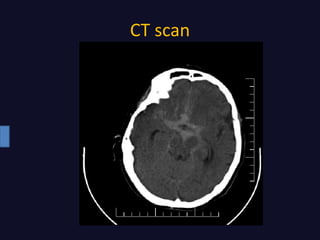

• CT scan

CT scan

Radiographic findings • CTscan • Cerebral Angiography • FLAIR* MRI • CT Angiography • MRA** *Fluid-attenuated inversion recovery **Magnetic Resonance Angiography